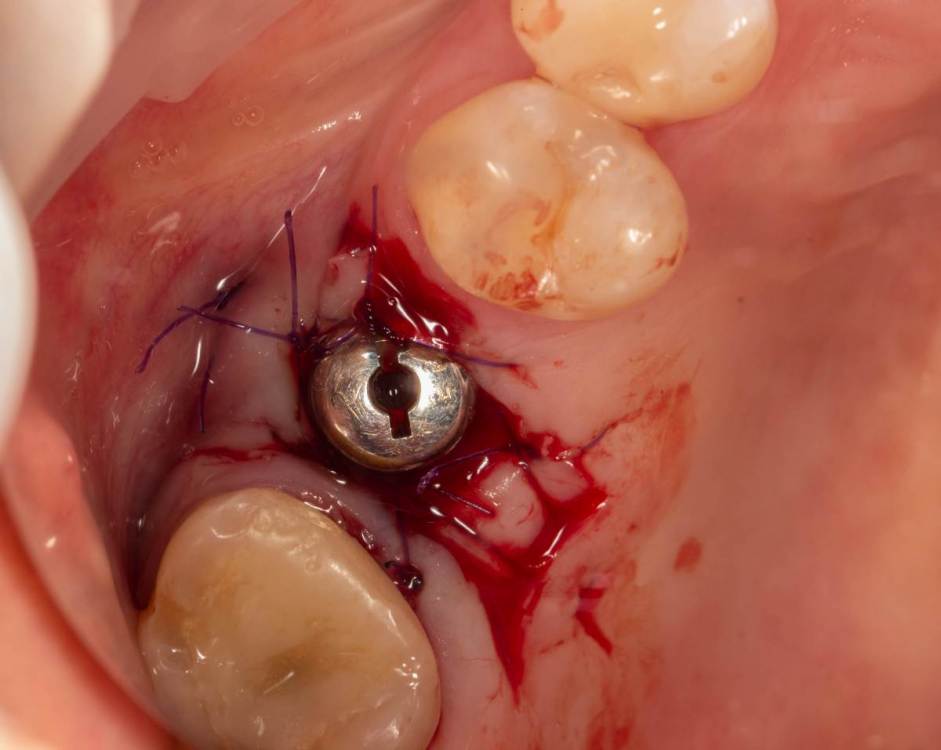

Женька Опубликовано 3 октября, 2022 Поделиться Опубликовано 3 октября, 2022 Открывал я снова тут имплантат roll техникой. И взбрело в голову, мол нёбно то много отрезал. Решил попробовать сделать скользящий нёбный лоскут. Как вы уже наверное догадались, ничего из этого не вышло . Лоскуток нёбный поначалу вроде даже смещался скользя, но далее превратился в СДТ маленький, который пришлось с определёнными трудностями возвращать хотя бы обратно на место (хорошо хоть не засосало в слюноотсос). Собственно вопрос, где и как можно данной методике научиться? может почитать где-то можно. У первоисточника хотелось бы, конечно) но трудно осуществимо. 1 Ссылка на комментарий